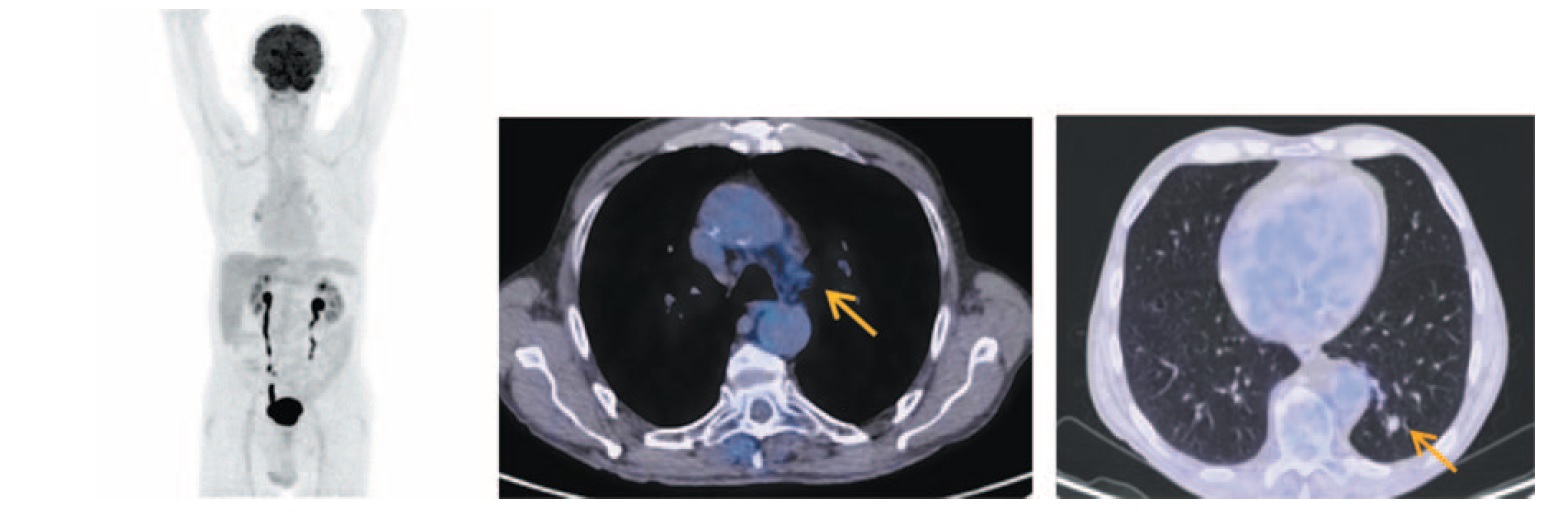

Продолжалась поддерживающая терапия атезолизумабом в дозе 1200 мг каждый 21-й день. Клинически признаков прогрессирования не отмечалось. После 16-го введения атезолизумаба выполнена очередная ПЭТ/КТ. В нижней доле левого легкого сохраняется тяж фиброза с узловым образованием в структуре размером до 12×10 мм без метаболической активности ФДГ. Сохраняются лимфоузлы аортопульмонального окна размером до 10 мм с фоновой фиксацией РФП (рис. 4). В соответствии с критериями RECIST v.1.1 у больного сохраняется полная регрессия опухолевого процесса, а по данным ПЭТ/КТ – полный морфо-метаболический ответ.

Рис. 4. Больной П., 76 лет, после 16 введений атезолизумаба (через 10 мес от начала лечения). На МIP- и аксиальных ПЭТ/КТ-проекциях в нижней доле левого легкого сохраняется тяж фиброза с узловым образованием в структуре размером до 12×10 мм без метаболической активности ФДГ. Сохраняются лимфоузлы аортопульмонального окна размером до 10 мм с фоновой фиксацией РФП. / Fig. 4. A 76-year-old patient P. after 16 injections of atezolizumab (10 months after the beginning of treatment). A band of fibrous tissue with a nodular formation in a structure measuring 12×10 mm without FDG metabolic activity in the lower lobe of the left lung is still detected on MIP- and axial PET/CT images. Aortopulmonary window lymph nodes measuring 10 mm with focal RFP uptake are still detected.

После 20-го введения атезолизумаба в дозе 1200 мг выполнена ПЭТ/КТ с 18F-ФДГ. В нижней доле левого легкого сохраняется тяж фиброза с узловым образованием в структуре прежней конфигурации и размером до 12×10 мм без метаболической активности ФДГ, равно как и лимфоузлы аортопульмонального окна с фоновой фиксацией РФП. По критериям RECIST v.1.1 у пациента сохраняется полная регрессия и полный морфо-метаболический ответ (рис. 5).

Рис. 5. Больной П., 76 лет, после 20 введений атезолизумаба (через 13 мес от начала лечения). На МIP- и аксиальных ПЭТ/КТ-проекциях в нижней доле левого легкого сохраняется тяж фиброза с узловым образованием в структуре прежней конфигурации размером до 12×10 мм без метаболической активности ФДГ и лимфоузлы аортопульмонального окна с фоновой фиксацией РФП. / Fig. 5. A 76-year-old patient P. after 20 injections of atezolizumab (after 13 months from the beginning of treatment). A band of fibrous tissue with a nodular formation in a structure of the same configuration measuring 12×10 mm without FDG metabolic activity and aortopulmonary window lymph nodes with focal RFP uptake in the lower lobe of the left lung are still detected on MIP- and axial PET/CT images.